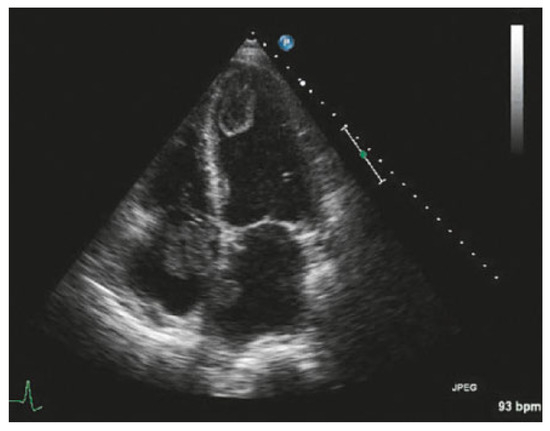

Value of Echocardiography in Differentiation of Acute Dyspnoea

by Ioannis Kapos and Felix C. Tanner

Echocardiography is one of the most effective imaging modalities for investigation of patients with acute dyspnoea. This review summarises appropriateness criteria and current guidelines for the use of cardiac ultrasound in common clinical scenarios presenting with acute dyspnoea, and illustrates such scenarios with [...] Read more.

Echocardiography is one of the most effective imaging modalities for investigation of patients with acute dyspnoea. This review summarises appropriateness criteria and current guidelines for the use of cardiac ultrasound in common clinical scenarios presenting with acute dyspnoea, and illustrates such scenarios with typical echocardiographic findings. Full article

Show Figures

Figure 1